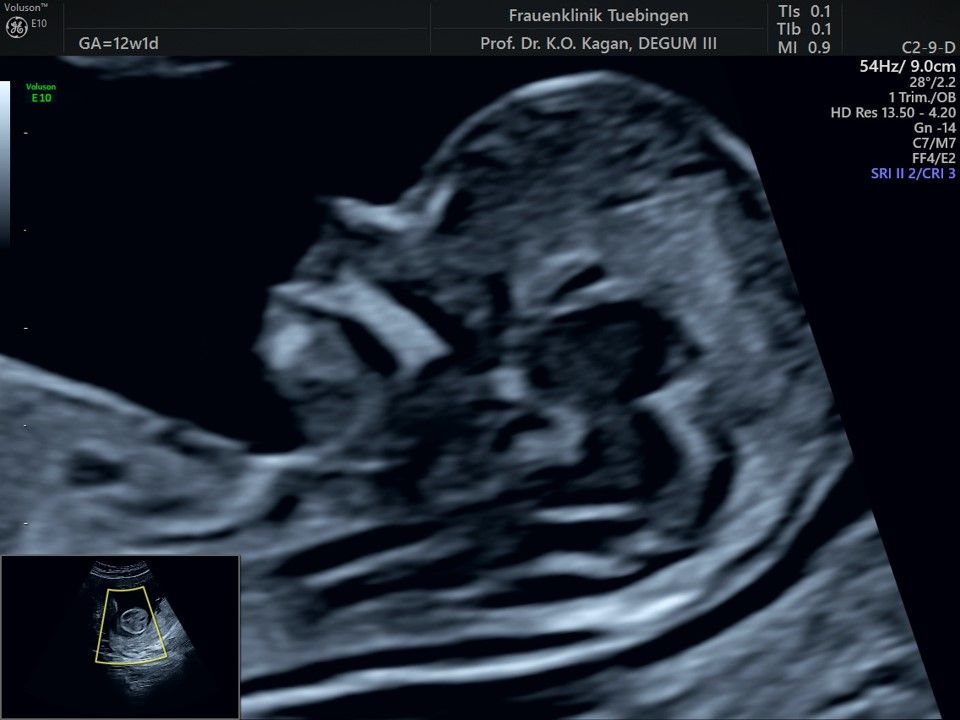

Im Rahmen des Ersttrimester-Screenings untersuchen wir die Organe des Feten mittels Ultraschall. Dabei machen wir auch gerne ein Bild für Sie.

Obwohl der Fet zu diesem Zeitpunkt erst zwischen 5 und 8cm groß ist, lassen sich bereits etwa die Hälfte aller schwerwiegenden Fehlbildungen erkennen bzw. ausschließen. Sollten wir eine Auffälligkeit sehen, werden wir mit Ihnen den Befund und das weitere Vorgehen ausführlich besprechen.

Fetale Anatomie

Das Ergebnis der Ultraschalluntersuchung ist wegweisend. Dabei wird der Fet vermessen, die Organe werden untersucht und die sonographischen Marker zur Risikoberechnung für Chromosomenstörungen werden beurteilt. Das sind: die Nackentransparenzdicke, Nasenbein sowie der Blutfluss in der rechten Herzhälfte und im Ductus venosus, einem Gefäß in der Leber des Feten.